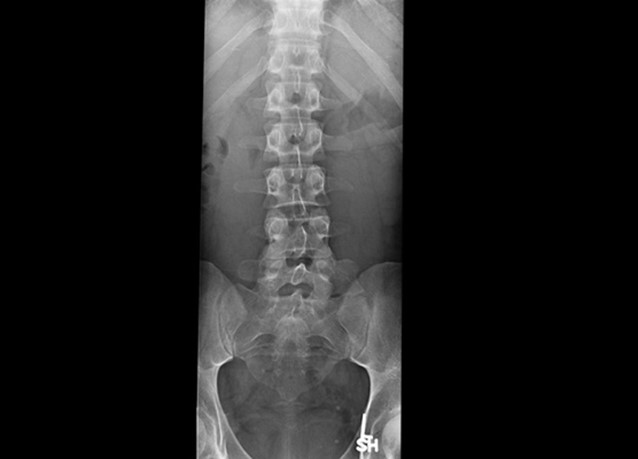

Case courtesy of Dr Hani Makky Al Salam, Radiopaedia.org, rID: 18568

Given the patient’s history of a fall along with spinal tenderness, you order an x-ray that shows an acute T12 compression fracture. Subsequent CT imaging shows an absence of ligamentous injury or cord involvement. Pain control is achieved using IM ketorolac, a lidocaine patch, and calcitonin nasal spray. Spine surgery is consulted and recommends non-operative management. The patient is instructed to follow up with her primary care physician and spine surgeon and endorses understanding.